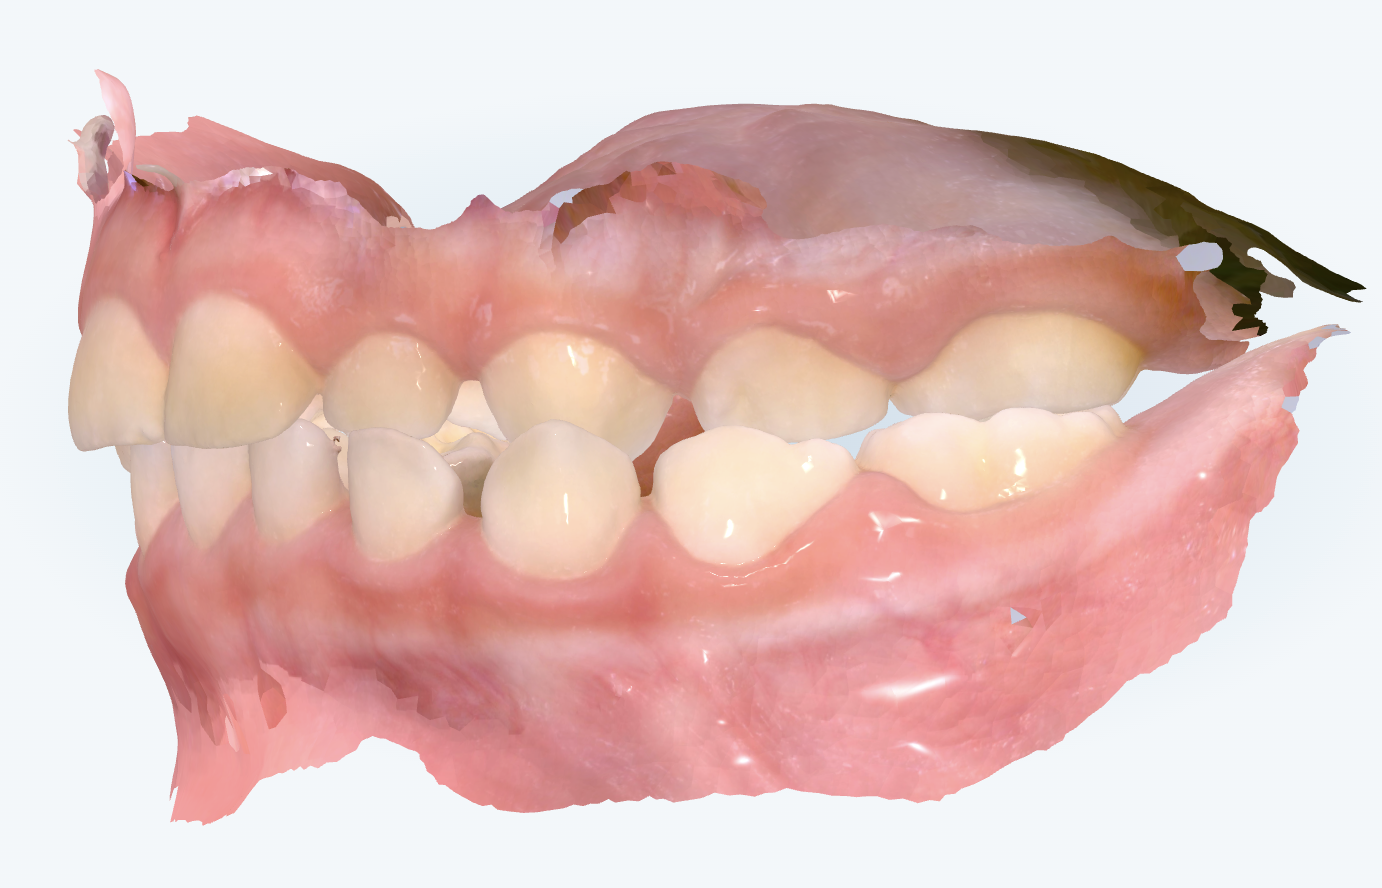

初診時の画像診断

左側の噛み合わせが上下反対に噛んでいました。下顎の左方向へのズレにより交叉咬合でした。

指吸いにより前歯は出っ歯傾向になっていました。

「確かに、左側の咬み合わせの中で上の歯より下の歯が前に出ている“交叉咬合”が見られますね。その影響で真ん中(正中)のずれがあり、全体的に下顎が左側へシフトしているようです。左側の奥歯の噛み合わせも上下が逆転しており、本来は上の歯が外側に来るはずが、下の歯が外に出てしまっています。このまま成長すると、下顎がその方向にさらに引っ張られ、顎全体がずれて成長してしまうリスクがあるため、できれば早めに対応していくのが望ましいですね。」